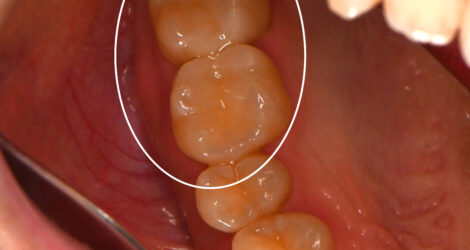

出来上がった被せ物

出来上がった被せ物